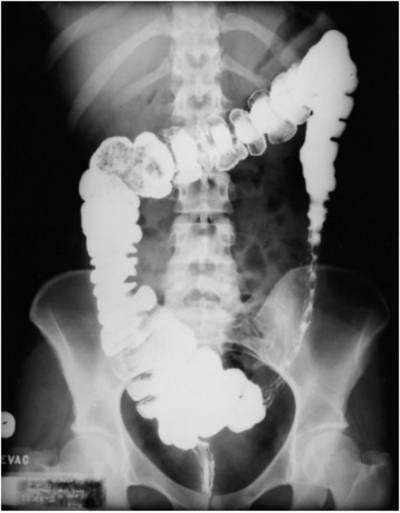

A 85-year-old man presents with severe crampy abdominal pain which is worse after eating, associated with frequent nausea, bloating and watery diarrhoea. His other medical problems include coronary artery disease, hypertension, hypercholesterolemia. He has a 40-pack-year smoking history. Barium enema is as shown. What is the most probable cause?

Explanation: ***Atherosclerosis of the mesenteric arteries*** - Classic presentation of **intestinal angina** with post-prandial crampy pain, nausea, and diarrhea in an elderly patient with multiple cardiovascular risk factors (smoking, CAD, hypertension). - Barium enema likely shows **thumbprinting pattern** characteristic of **ischemic colitis**, caused by compromised mesenteric blood flow from atherosclerotic narrowing. *Left ventricular aneurysm* - This is a **cardiac complication** that doesn't directly cause gastrointestinal symptoms or bowel ischemia. - Would present with **heart failure symptoms** like dyspnea and chest pain, not abdominal pain and diarrhea. *Transmural inflammation of the small intestine* - Describes **Crohn's disease**, which typically presents in **younger patients** with chronic symptoms and **skip lesions**. - Would show **cobblestone appearance** and strictures on imaging, not the thumbprinting pattern of ischemic colitis. *Progressive pancreatic inflammation* - Refers to **chronic pancreatitis**, which causes **epigastric pain** radiating to the back and **steatorrhea**. - Would show **pancreatic calcifications** and ductal changes on imaging, not colonic thumbprinting on barium enema.